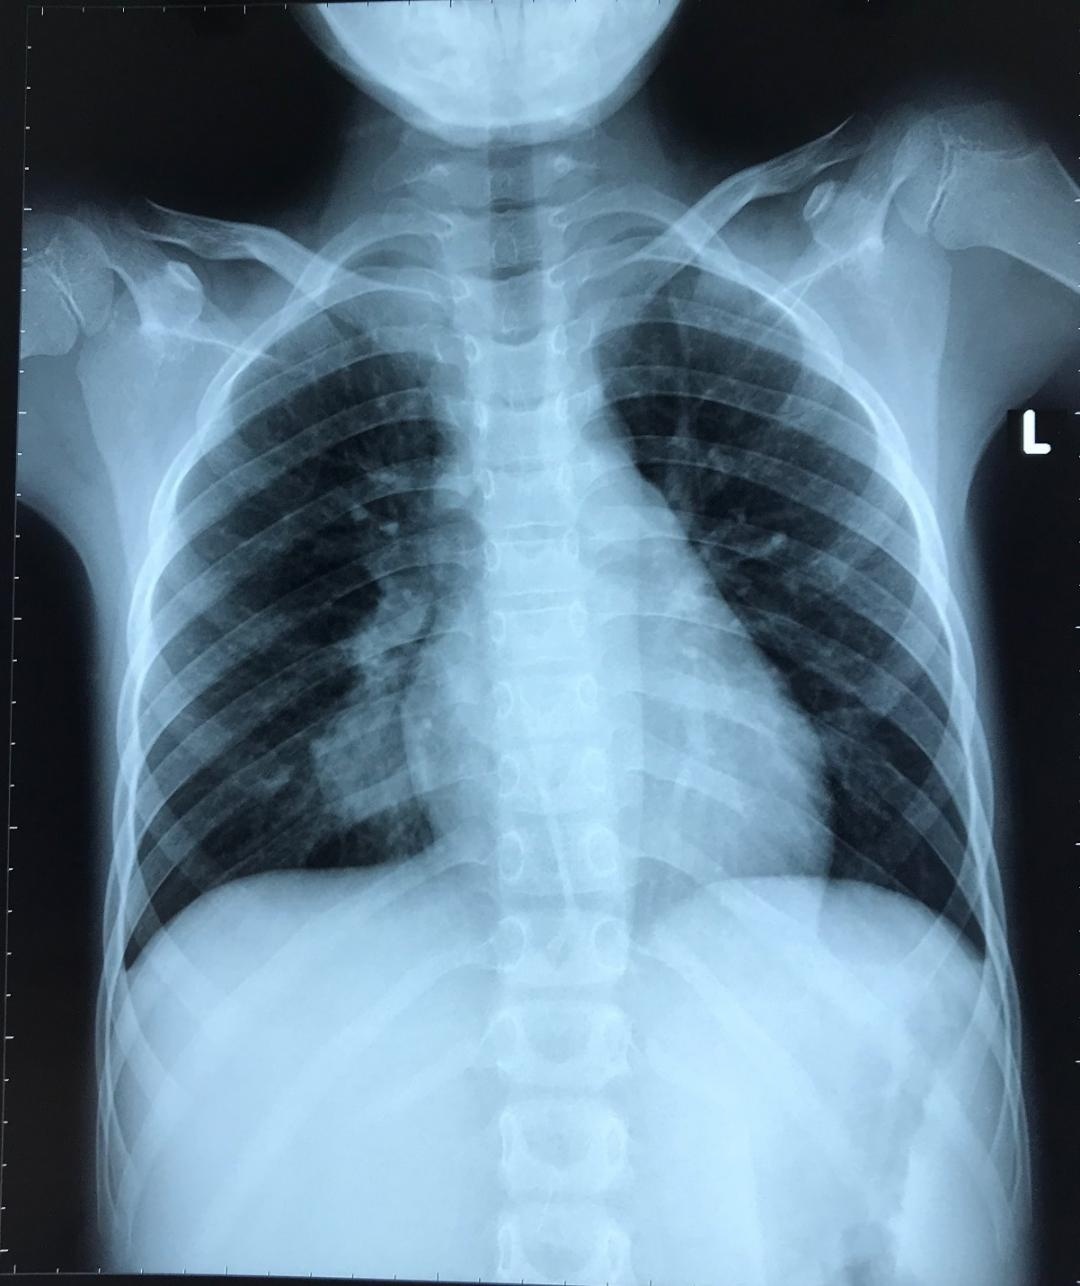

| Hình ảnh Xquang của bệnh nhi trước khi được can thiệp - Ảnh: BVCC |

Tại bệnh viện Nhi Đồng 2, bệnh nhân được chụp lại CT ngực, phát hiện thấy túi phình động mạch phổi ở thùy dưới phổi phải, kích thước 20x18 mm. Bệnh nhân được làm đầy đủ các xét nghiệm để tìm nguyên nhân gây giãn động mạch phổi. Kết quả khám lâm sàng và xét nghiệm gợi ý bệnh nhân mắc chứng bệnh Behçet, đây là bệnh tự miễn hiếm gặp gây nên nhiều biểu hiện trong đó có giãn động mạch phổi.